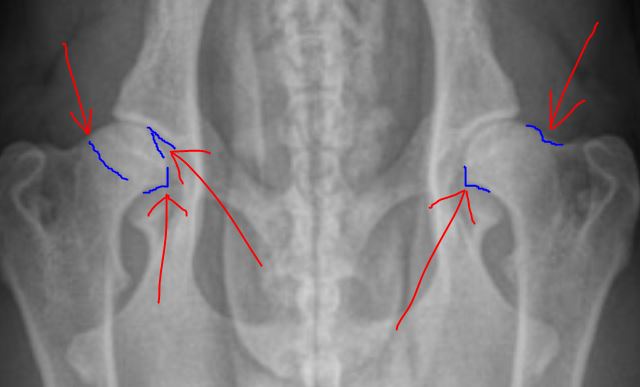

how near was she to a heat cycle? left looks very good. right is at least fair, possibly good. i don't see anything

that should cause concern. she should be able to perform well in any discipline. if you do the ofa @ 24 mo, i would

Thanks for the input. I sent in prelims to OFA and they said mild dysplasia. It looks good to me and I had two different Vets agree. Anyone else have an opinion that would be much appreciated?

i truly don't agree with dysplastic. no doubt that right hip could be better, but half the femur head is in the socket & that is why i say the dog should

I agree with OFA. The heads are losing their round shape and there is some remodeling. The edges of the sockets are beginning to deviate cranially and the necks are not well defined; they are as wide as the heads.

Positioning is not correct,with better positioning hips may look better.

these are the areas I find trouble with.

these hips graded as good.